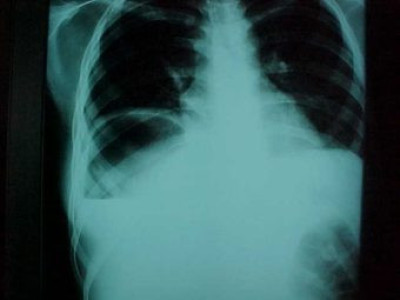

Abcseso Subfrénico

Envíado por Dr. Carlos Edgardo Escobar